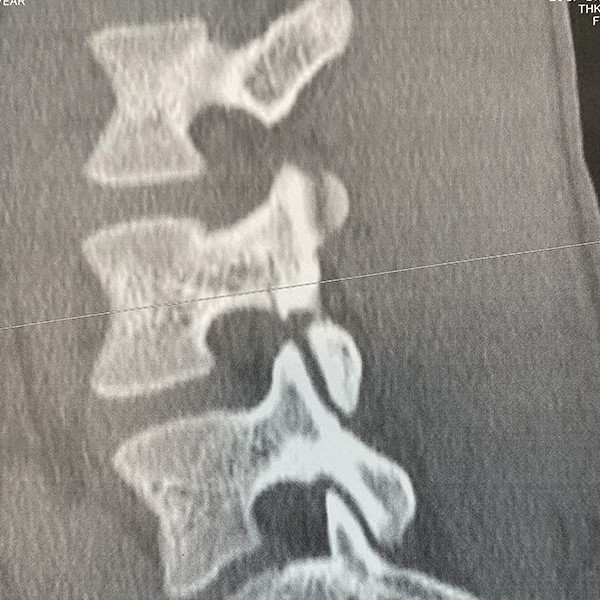

1ヶ月後のCT画像